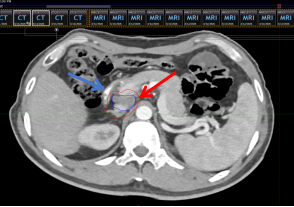

图3 未植入隔离胶定位CT(红色箭头为下腔静脉靶区,蓝色箭头为十二指肠)